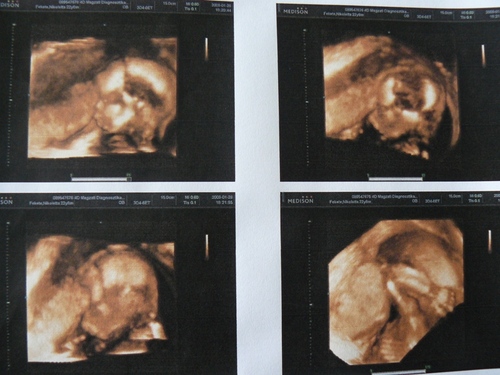

szonibaba!

Ezek igazi babamozis képek!

(Na ez az, amihez nekünk még egyszer sem volt szerencsénk.

)